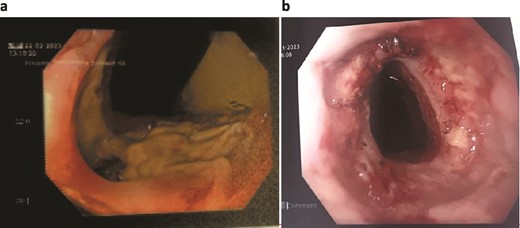

A 89-year-old male, diagnosed with Boerhaave syndrome and oesophageal perforation was transferred from one hospital to another on day 13 post-diagnosis. Initial diagnostic tests, including a gastrografin swallow, identified a defect in the distal left lateral wall of the oesophagus, measuring ˂1 cm with an extraluminal component of at least 5 cm (Fig. 2a).

Patient Two: (a) Before VACStent insertion, showing the oesophageal defect. (b) After VACStent treatment, demonstrating successful defect closure.

On day 14 post-diagnosis, the patient underwent an oesophago-gastro-duodenoscopy (OGD) and VACStent insertion, which was kept in place for 6 days. A CT thorax on day 16 post-diagnosis confirmed proper placement of the VACStent with no ongoing leak (Fig. 2b). The patient underwent ultrasound-guided drainage for a left pleural effusion on day 17 post-diagnosis and remained nil by mouth. Subsequent imaging showed a decrease in the oesophageal defect size, and by day 22 post-diagnosis, the patient was advised to start a soft moist diet, which was well tolerated.